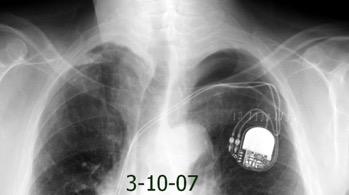

Síndrome de afectación postcardiaca (postcardiac injury)

Post infarto 1-7 % (Dressler)

Trauma cerrado Implantación marcapasos

Cirugía cardiaca. 17-31% (Post.pericardiotomía)

3707 pacientes 29 Derrames (0,78%) > de 25% del hemitórax

Todas menos 2 Izdos.

Angioplastia

By-pass coronario 21-10-03